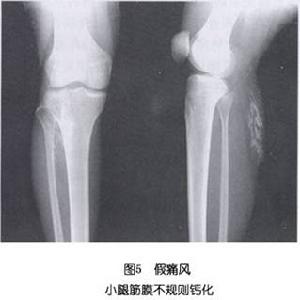

痛風和鈣化性肌腱炎有時不易區分,臨床上都有炎症,X線有時都有軟組織腫脹和鈣化,且對秋水仙鹼治療都有效。痛風有時可伴有骨侵蝕現象,而鈣化性肌腱炎則無。